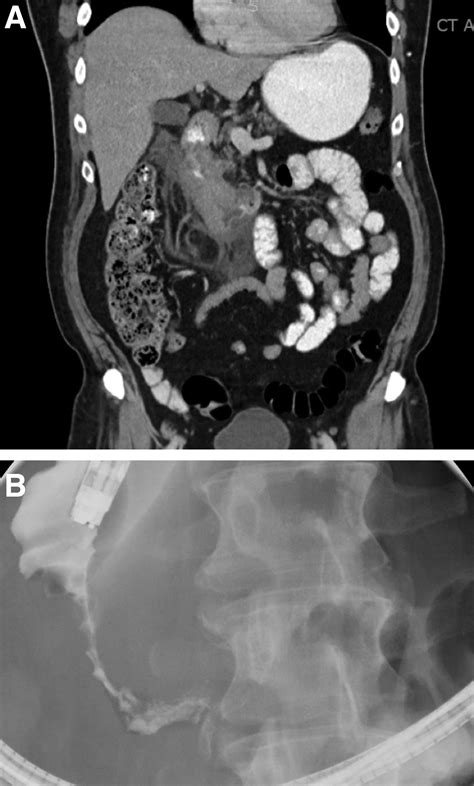

An Apple Core Lesion is a term used to describe a specific type of lesion that appears as a central area of necrosis surrounded by a rim of enhancing tissue. This appearance is often compared to the core of an apple, hence the name. The lesion is typically found in the context of certain types of cancer, particularly colorectal cancer, but can also be seen in other conditions.

• CT Scan: A computed tomography (CT) scan provides detailed images of the internal structures of the body. It can help identify the presence and extent of an Apple Core Lesion.